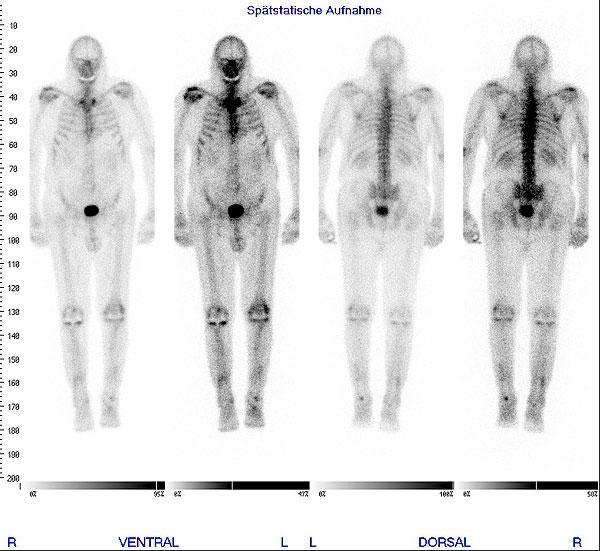

Skelett

bei gutartigen (lokalen oder generalisierten Knochenstoffwechselstörungen, Prothesenlockerungen, Insuffizienzbrüchen, Entzündungen) oder tumorösen Erkrankungen (Metastasensuche, Verlaufskontrolle)